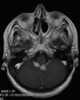

Linear meningeal enhancement